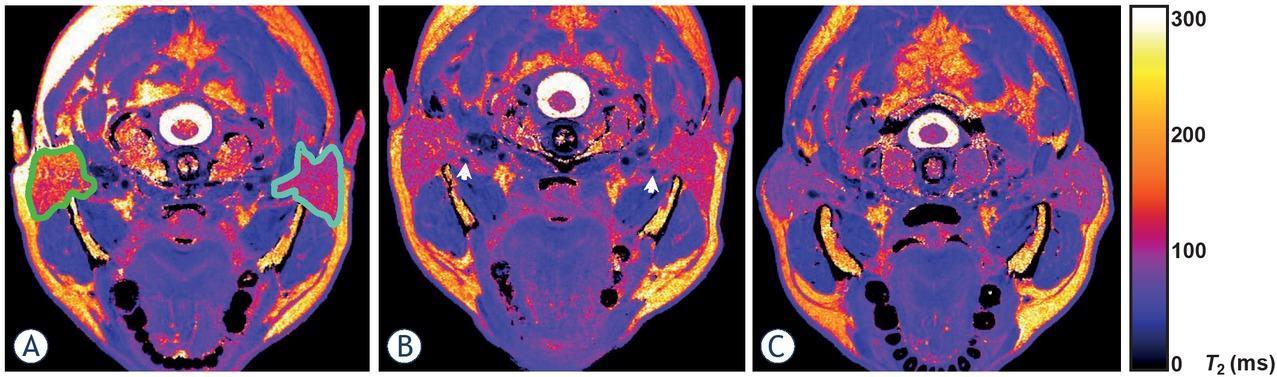

Figure 1

Figure 2

Figure 3

Figure 4